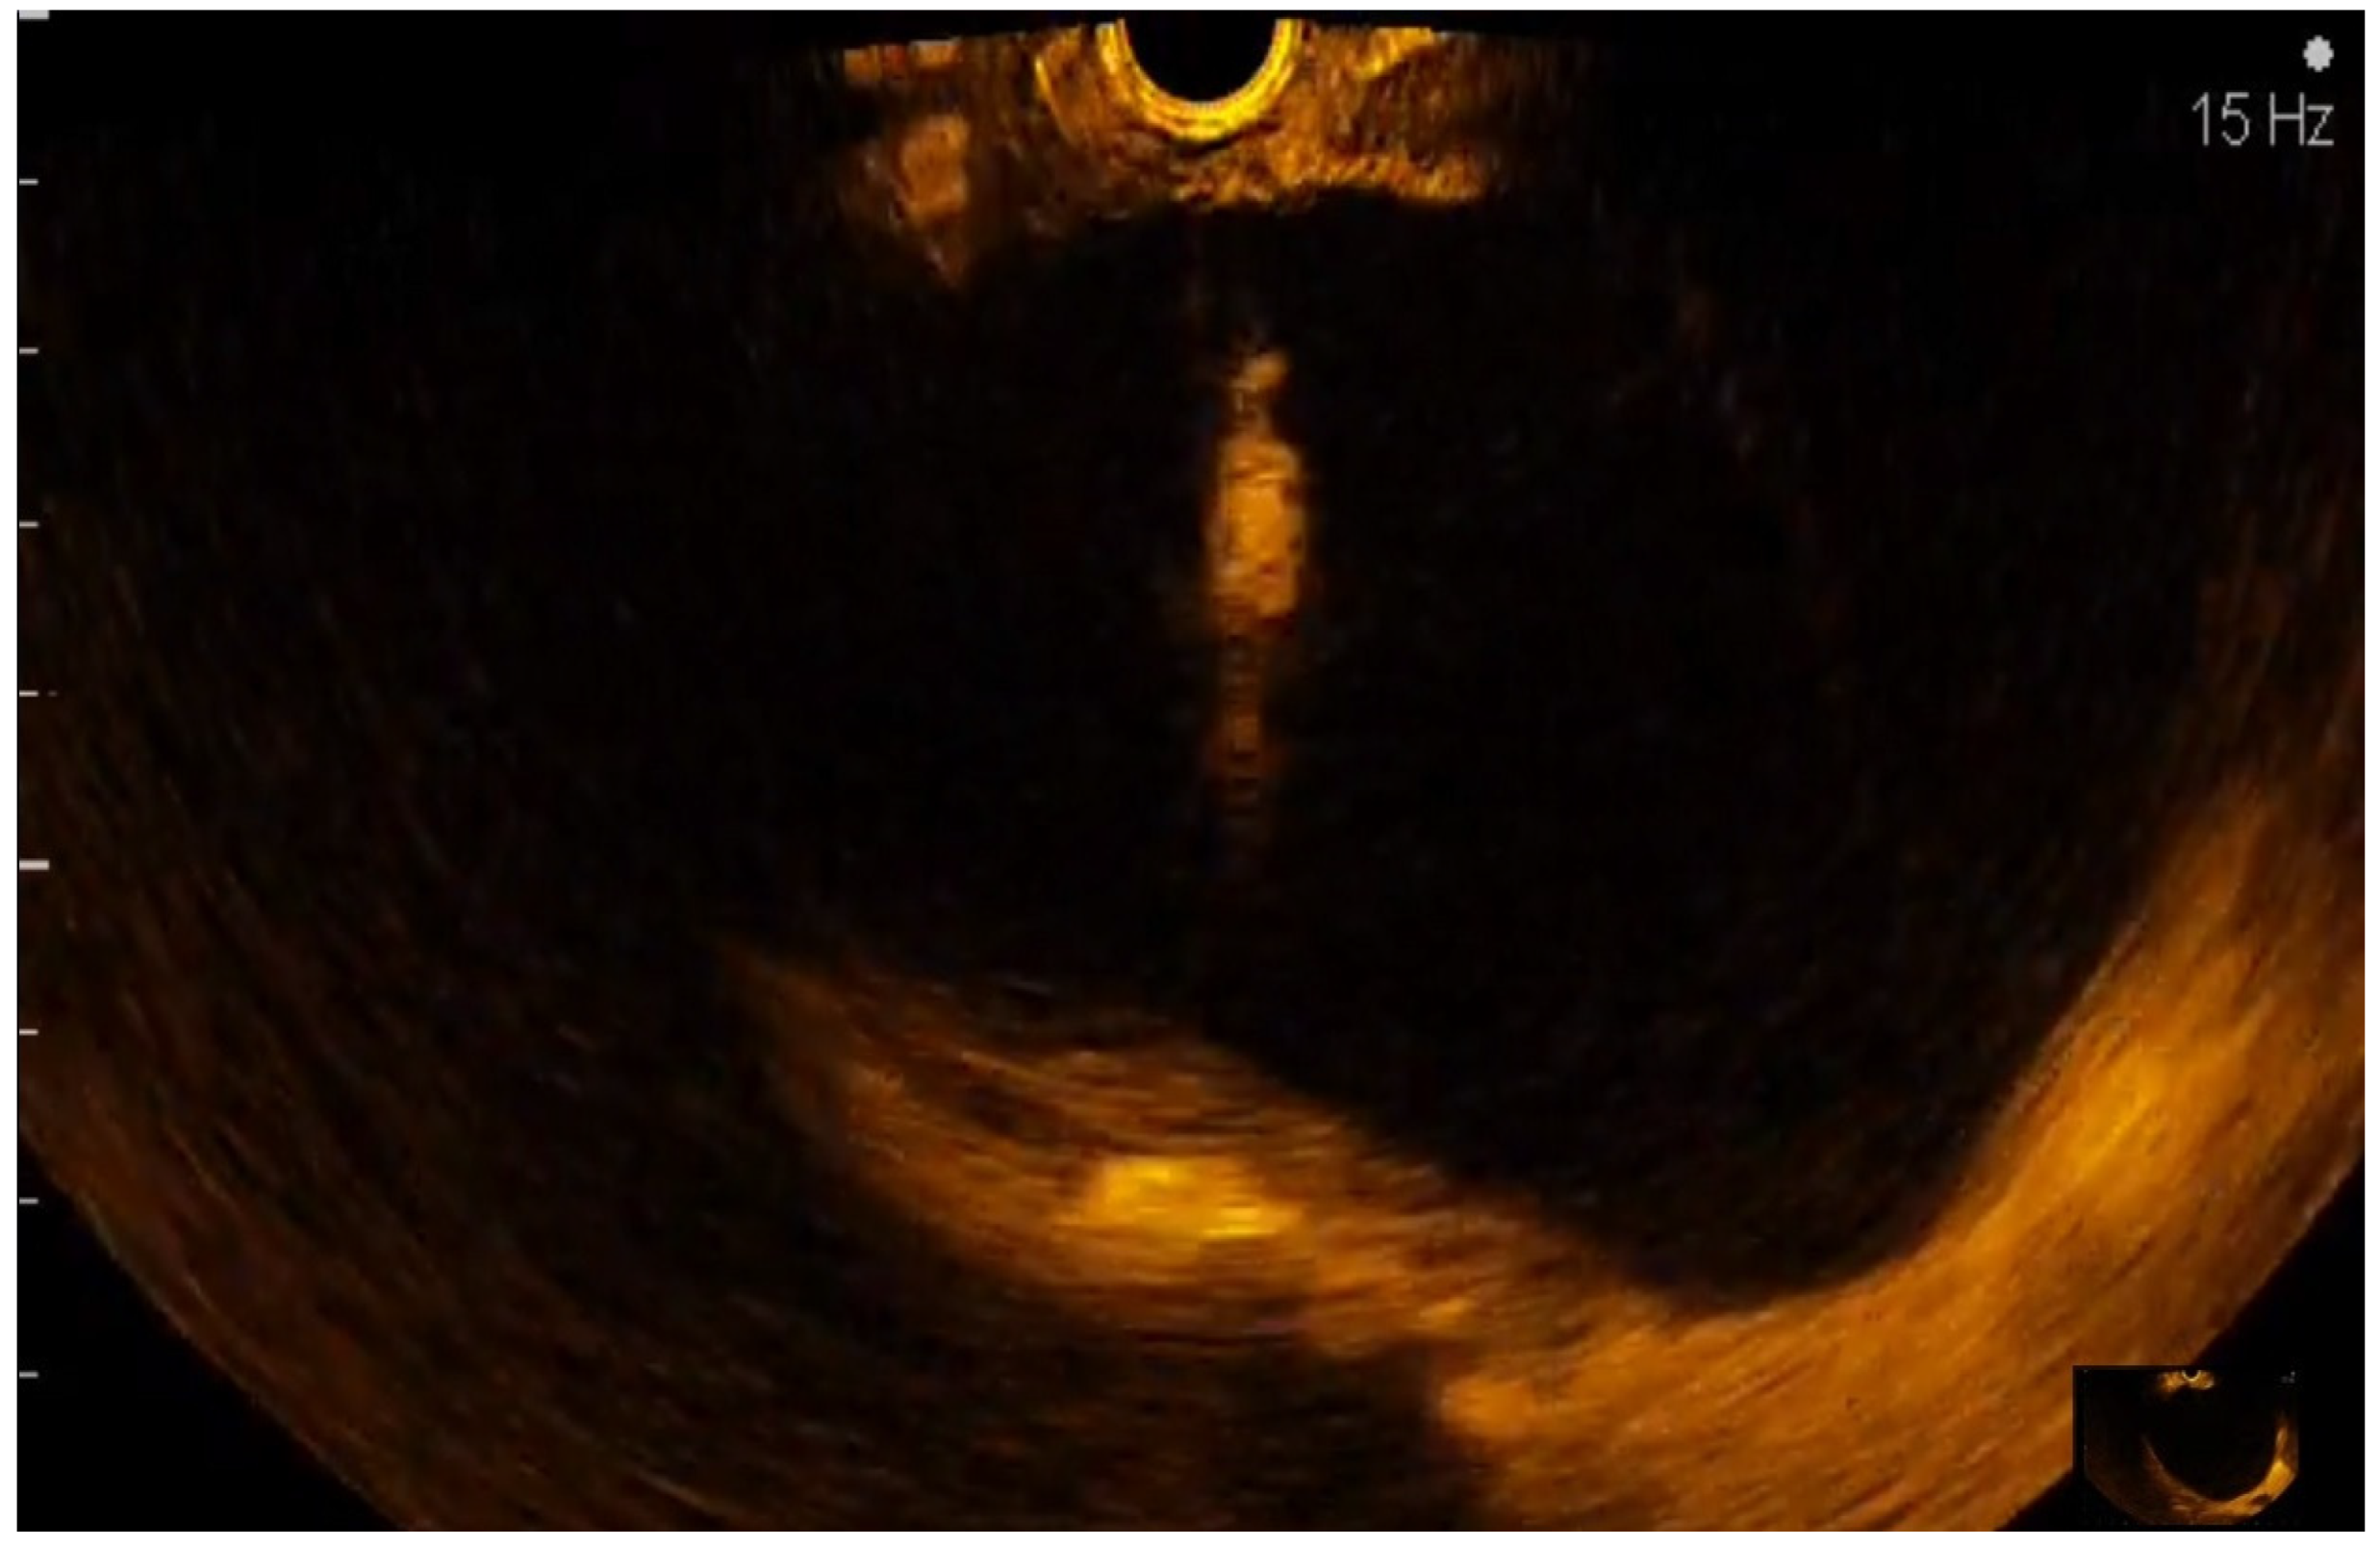

CE-EUS image of a pNET revealing an isoenhancing solid mass in the arterial phase and a discrete wash-out in the venous phase.

Figure 6.

CE-EUS image of a pNEC (pancreatic neuroendocrine carcinoma) with aspect in the arterial phase and wash-out in the venous phase.